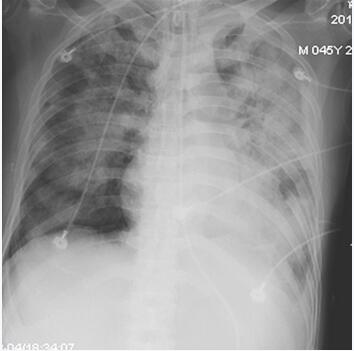

辅助检查:复查胸部X线、CT提示双肺广泛感染伴双侧胸腔积液(图63-1、图63-2)。

图63-1 起病第19天(入笔者医院当天)胸片提示两肺广泛感染

诊治经过:应用亚胺培南-西司他汀钠0.5g,每8小时1次静脉滴注、利奈唑胺0.6g,每12小时1次,静脉滴注联合抗感染,纤维支气管镜反复吸痰,适当控制液体量、减轻心脏负荷治疗。床边超声心动图示主动脉瓣二叶式畸形、主动脉瓣中度狭窄伴轻度反流,左心肥大,二尖瓣中度反流,三尖瓣轻至中度反流,中度肺动脉高压,EF 55%。经治6天后患者全身毒血症状有所减轻,氧合功能改善(机械通气下FiO2 45%,PEEP 5cmH2O,SPO2 96%),全身感染及心功能相关指标较入笔者医院时好转(2月22日:WBC 16.8×109/L,CRP 75.3mg/L,NT-ProBNP 4462pg/ml;2月28日:WBC 12.7×109/L,CRP 29.8mg/L,氨基酸B型利钠肽原NT-ProBNP 2222pg/ml)。但体温仍在38.5℃左右波动,床边胸片(2月28日):两肺广泛感染病灶,较2月22日胸片似有吸收(图63-3)。

3月4日体温骤高至39.5℃,两日来心率持续波动于130~140次/分,全身感染及心功能相关指标进一步上升(WBC 18.8×109/L,CRP 112.5mg/L,NT-ProBNP 6620pg/ml)。经笔者医院感染科会诊,遂加用伏立康唑0.4g,每12小时1次静脉滴注抗真菌,甲泼尼龙40mg,每日1次静脉滴注促进肺部坏死组织吸收。至傍晚患者出现心率减慢、血压下降,氧饱和度下降,予补液、强心、升压等治疗后未见好转。床边胸片:双肺广泛感染灶(图63-5)。之后出现心脏骤停,经持续近3小时的心肺复苏无效,最终死亡。

图63-5 起病第29天(入笔者医院第11天)胸片示两肺广泛感染病灶